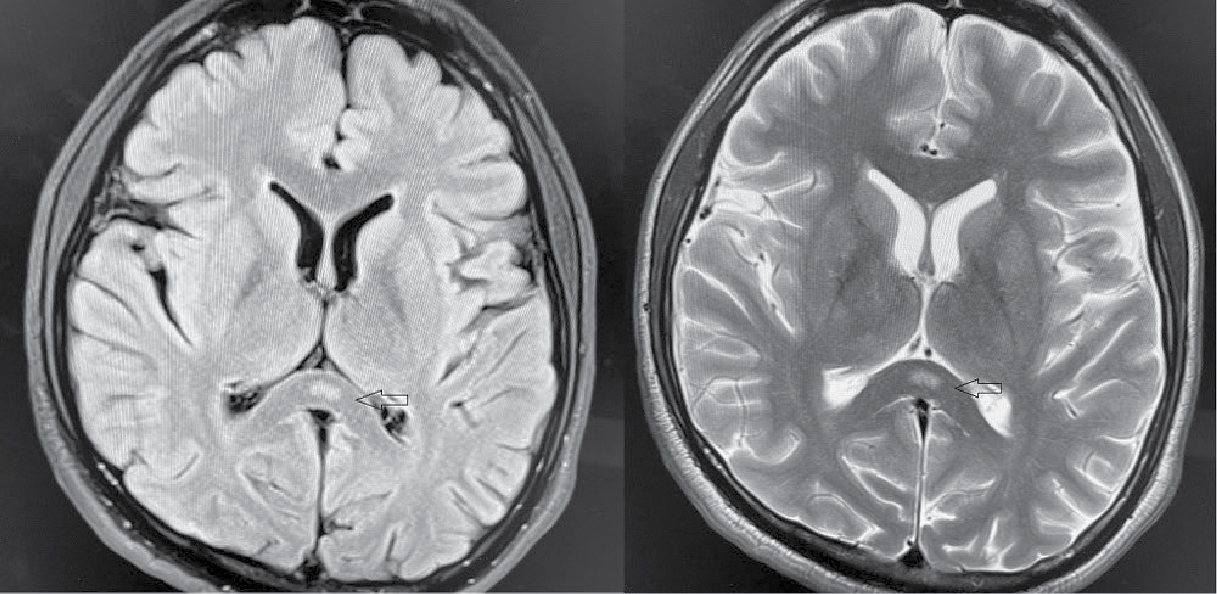

In view of that, patient underwent magnetic resonance imaging (MRI) brain, which showed focal areas of acute diffusion restriction signal intensity in the splenium in the midline portion, appearing hyperintense on diffusion-weighted image (DWI)/T2/FLAIR (fluid-attenuated inversion recovery) images with a drop in signal intensity on apparent diffusion coefficient (ADC) mapping, findings consistent with acute ischemic infarct (Fig. 1). His 2D echocardiogram was normal with no left ventricular dysfunction or evidence of thrombi. His carotid duplex ultrasound was also normal. Conservative management was continued and his acute confusion state recovered subsequently.

Figure 1. Focal areas of acute diffusion restriction signal intensity in the splenium in the midline portion (marked by arrow), appearing hyperintense on DWI image, findings consistent with acute ischemic infarct in splenium of corpus callosum.